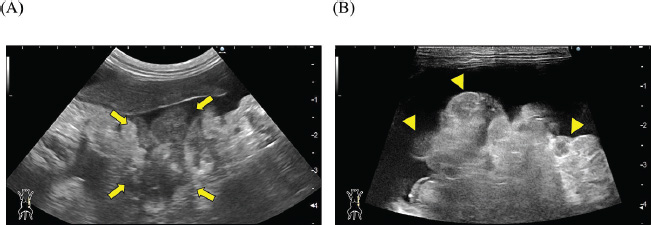

A 2-year-old castrated male domestic shorthair cat, weighing 5.3 kg, presented with a 2-month history of abdominal distension and a 4-day history of anorexia. There was no history of illness or abdominal surgery. Physical examination revealed severe abdominal distension with a fluid wave and mild hypothermia (37.1°C). Blood tests revealed mild elevations in blood glucose (178 mg/dl; reference interval 71–148 mg/dl) and serum amyloid A (5.27 µg/ml; reference interval <3.75 µg/ml) levels, while lipase activity was within normal limits (23.9 U/l; reference interval <30 U/l). Abdominal radiography revealed increased radiopacity and digestive tract consolidation (Fig. 1). Abdominal ultrasonography revealed severe ascites, small intestine hypoperistalsis, pancreatic enlargement, and irregular thickening of the peritoneum with several nodules (Fig. 2). Echocardiography revealed no abnormality. In the ascitic fluid analysis, the total nucleated cell count was 1,000 cells/μl with no evidence of neoplastic cells or bacterial infection, and the specific gravity of the supernatant was 1.024, confirming the ascites as a modified transudate (Fig. 3). Feline infectious peritonitis was considered unlikely due to the absence of feline coronavirus genes in the ascitic fluid and no elevation in blood anti-coronavirus antibody titers. Based on the imaging findings, such as peritoneal thickening, gastrointestinal tract consolidation, and severe ascites, EPS was initially suspected. These findings are consistent with the typical presentation of EPS, characterized by fibrotic thickening of the peritoneum and encasement of abdominal organs (Gremillet et al., 2022). However, the possibility of malignancy was deemed unlikely due to the cat’s relatively young age. A trial treatment with prednisolone (10 mg/head, q24 h) and enrofloxacin (25 mg/head, q24 h) was initiated to manage the suspected inflammatory process and potential bacterial infection, respectively. However, no clinical improvement was observed, suggesting that the underlying condition might be more complex than initially suspected. A non-sedated computed tomography (CT) scan was performed to obtain more detailed diagnostic information on day 12 after presentation. A Siwtenn-slice multi-slice CT scanner (Aquilion™ Lightning, Canon Medical Systems, Japan) was used without anesthesia, with the patient restrained in an acrylic cage (CT capsule, Terucom, Japan). The following technical parameters were used: rotation time=0.75 s; slice thickness=1 mm; reconstruction interval=0.5 mm; table speed=16 mm/rotation; helical pitch=16.0; X-ray tube voltage=120 kV; and X-ray tube current=100 mA. The CT scan revealed a tumor-like enlargement of the pancreas, irregular scattered nodular formations aggregating dorsally in the peritoneum, and ground-glass opacity in the right lower lobe of the lung (Fig. 4). Because angiography was not performed, the vascular characteristics and more detailed differentiation of the soft tissue masses could not be assessed. A pancreatic tumor was suspected; however, diagnostic and therapeutic surgical interventions were deemed difficult due to the animal’s condition. In addition, the owner declined further invasive procedures, such as fine-needle aspiration or laparoscopy. Despite prednisolone treatment (5 mg/head, 24 h), ascitic fluid drainage, and fluid therapy, the cat died 19 days after the first presentation.

Fig. 1. Abdominal radiographs. (A) Right lateral and (B) ventrodorsal radiographs are shown. The images show severe abdominal distension and a generalized decrease in contrast, suggesting ascites. Mild gas retention and clustering of the intestines were observed (arrow).